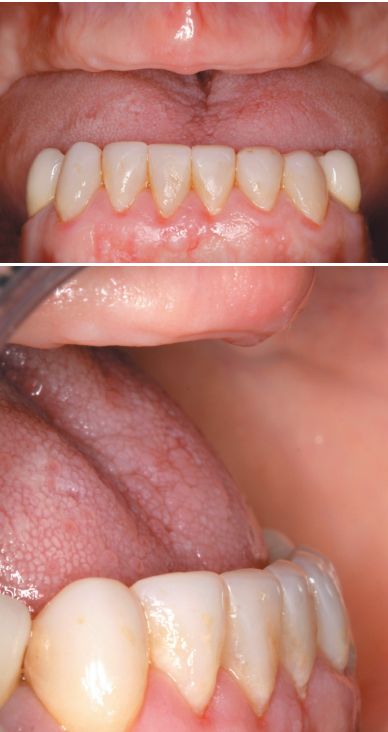

We present the clinical case of a 56-year-old female patient, who has been wearing an upper complete removable prosthesis and a lower partial prosthesis for more than 20 years. She comes for consultation requesting implant rehabilitation to replace her current prosthesis to improve her masticatory function. In the intraoral examination we can observe that the prosthesis meets quite satisfactorily the aesthetic requirements of the patient, but according to her, they move when chewing. When removing the prosthesis, a maxillary edentulous ridge with an evident centripetal resorption that has left the starting situation close to that of a skeletal class III (Figures 1 and 2).

To start the diagnostic phase, a panoramic radiograph is performed that gives us an idea of the general condition of both jaws to start the treatment plan.

It shows that there is apparently some height in the maxillary ridge both anterior and posterior and a low dental nerve in the jaw that allows us to have a greater residual bone crest available for the insertion of the implants (Figure 3).